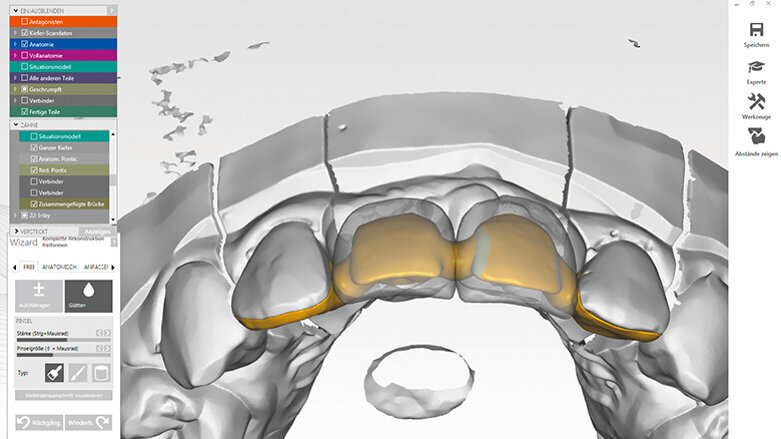

U zubu 22 bylo provedeno endodontické ošetření. Tato skutečnost podstatně omezila protetické možnosti a měla negativní efekt na prognózu zubu. Podle vývojového stadia cervikálních obratlů stanovovaného ortodontistou prostřednictvím laterálního cefalometrického rentgenologického snímku bylo odhaleno, že je možné očekávat pouze minimální transverzální a horizontální růst u této pacientky. Na základě této skutečnosti a malé protetické hodnoty pilířového zubu 22 se protetický ošetřující tým po konzultaci s pacientkou rozhodl pro celokeramický adhezivní můstek se dvěma křidélky adhezivně fixovanými na zuby 12 a 22. Cílem tohoto ošetření byl odklad implantace na tak dlouho, jak jen to bude možné, tedy do kompletního ukončení růstu mladistvé pacientky. Prostřednictvím fixní rekonstrukce tým usiloval o nejlepší možnou podporu a zachování s defektem sousedících měkkých a tvrdých tkání.

Po odstranění fixního ortodontického aparátu byly původní rekonstrukce laterálních řezáků nahrazeny novými kompozitními dostavbami. Preparace na těchto zubech již byla provedena, když byl zhotovován předchozí metalokeramický můstek. Proto nebylo nutné dodatečně odstraňovat velká množství zubních struktur – palatinální preparace však vyžadovaly zahlazení. Gingiva byla ošetřena retrakční pastou. Otisk byl zhotoven pomocí skeneru 3M True Definition a odeslán do 3M frézovacího centra. Pacientka obdržela snímatelnou provizorní náhradu (obr. 5).